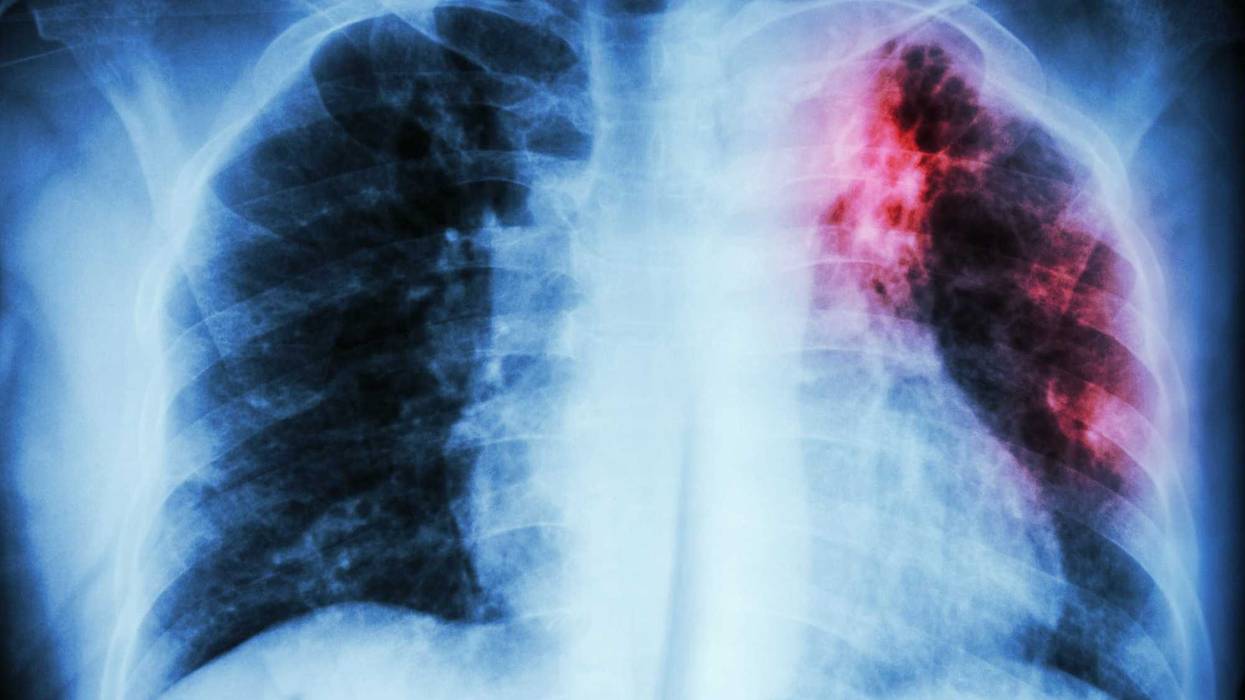

For the first time on over a decade, global tuberculosis deaths have increased, according to the World Health Organization.

Approximately 1.5 million died from the disease – an infectious bacterial disease that mainly impacts the lungs – last year worldwide, said the WHO.